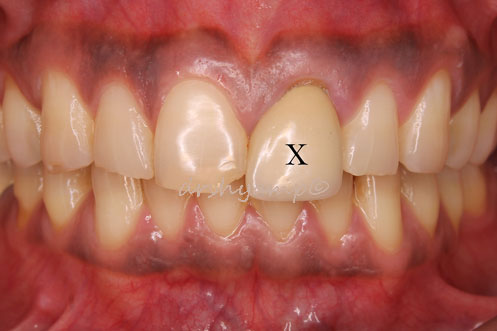

Cyst Enucleation